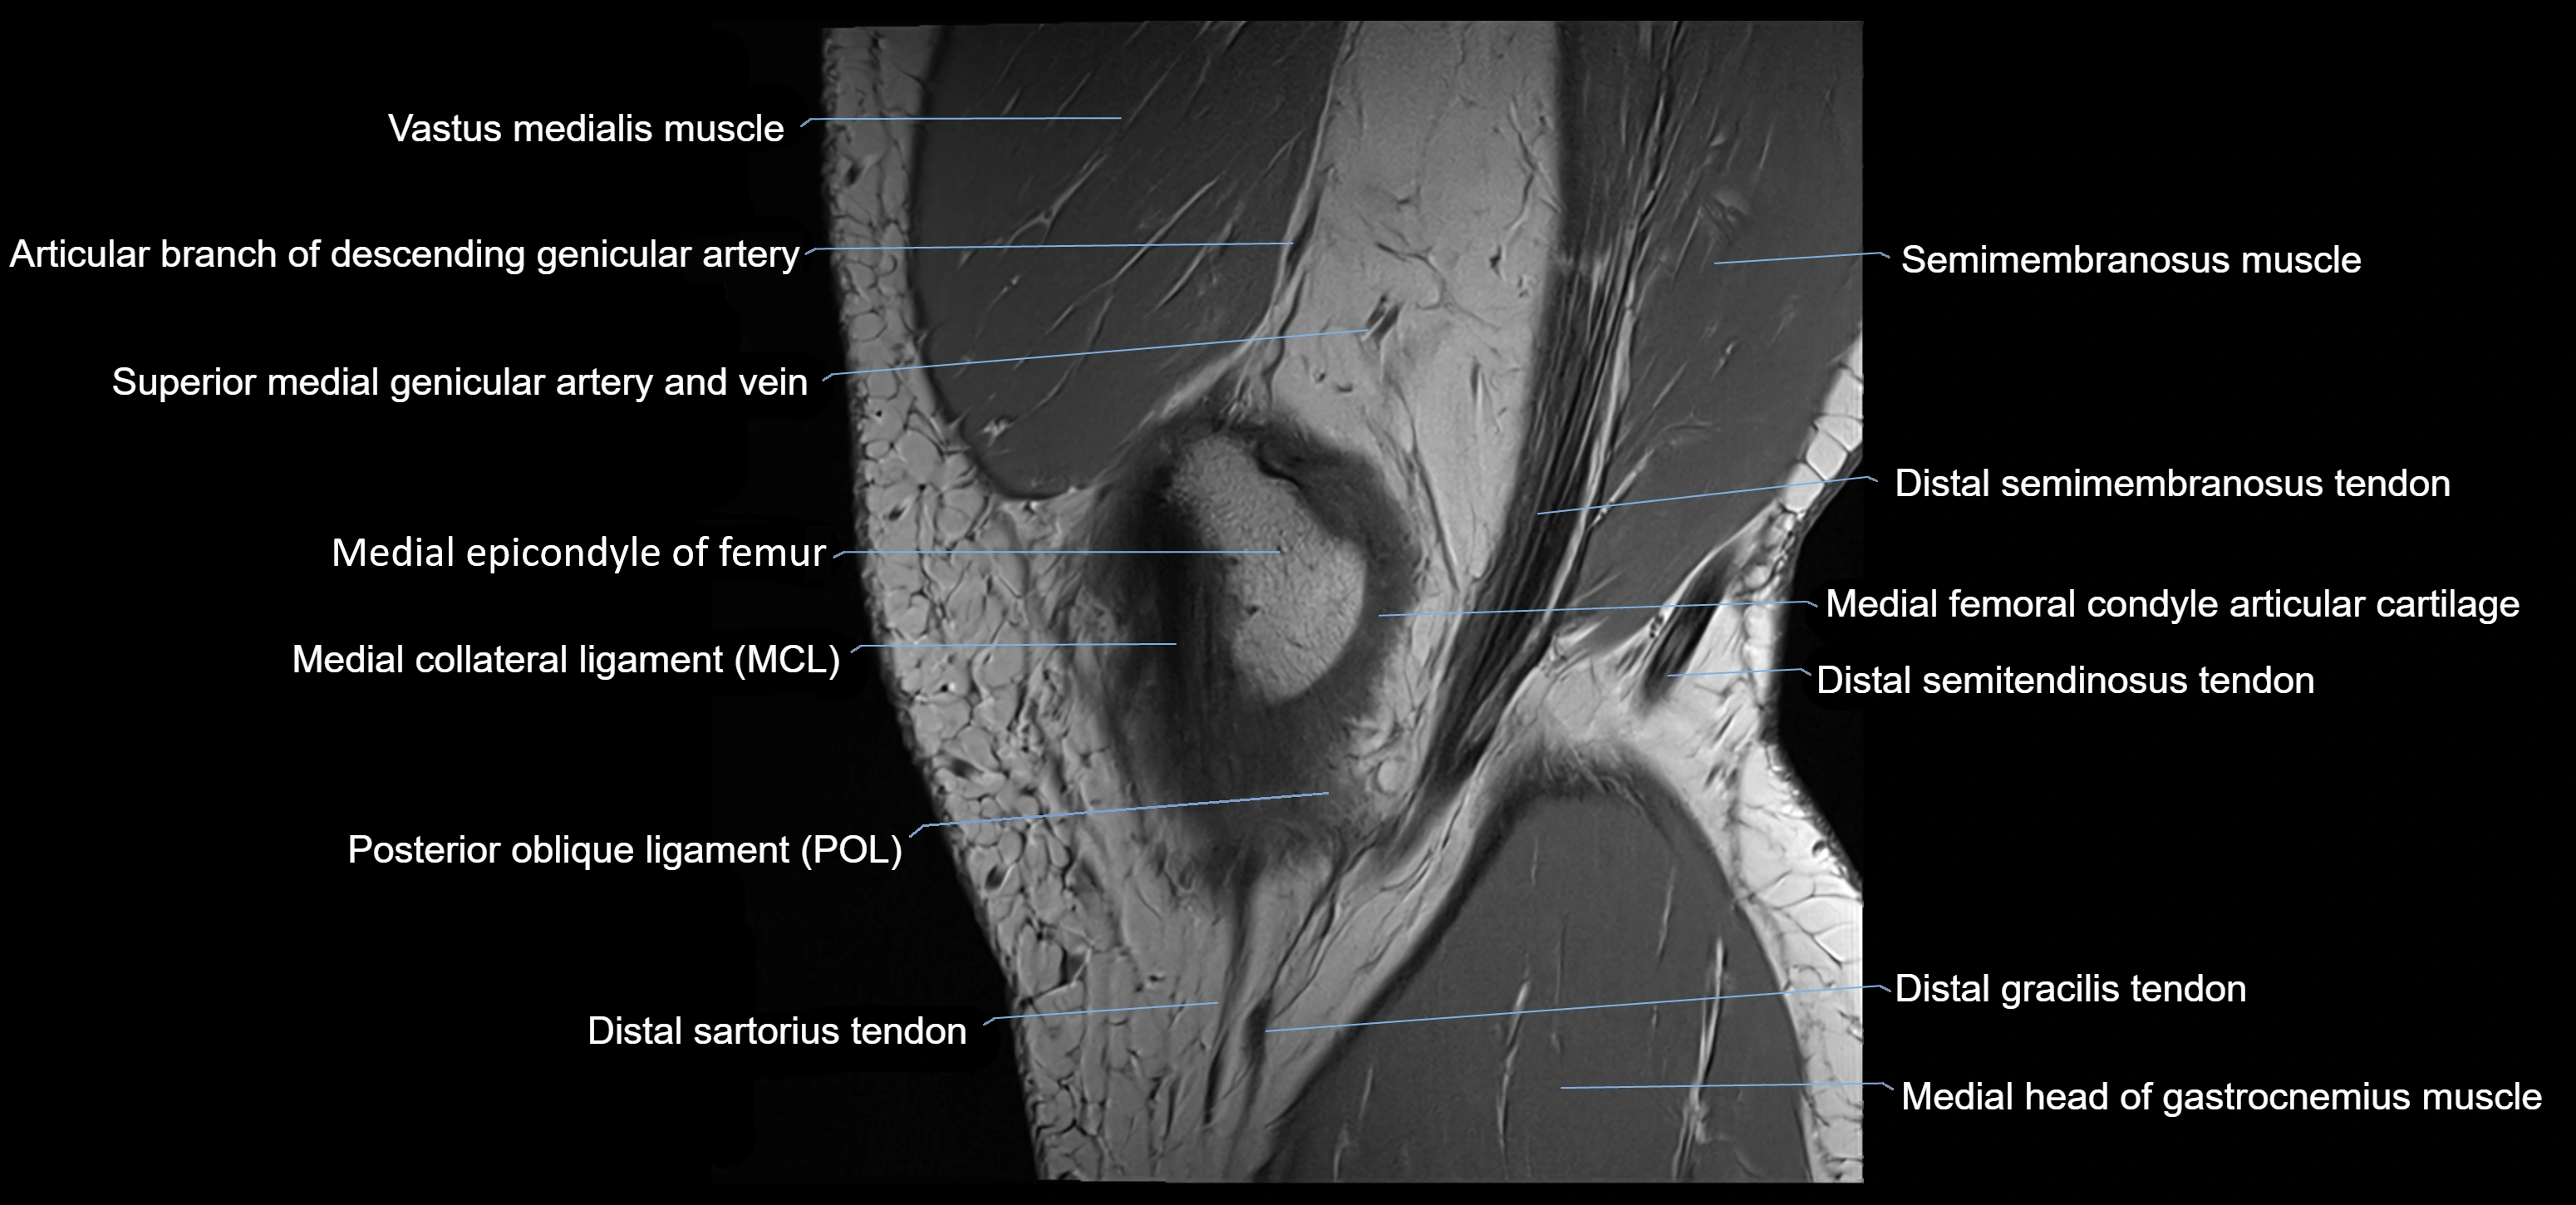

- Distal semimembranosus tendon

- Distal semitendinosus tendon

- Gracilis tendon (Distal)

- Knee Joint

- Medial collateral ligament

- Medial epicondyle of femur

- Medial head of gastrocnemius muscle

- Oblique popliteal ligament

- Semimembranosus muscle

- Superior medial genicular artery